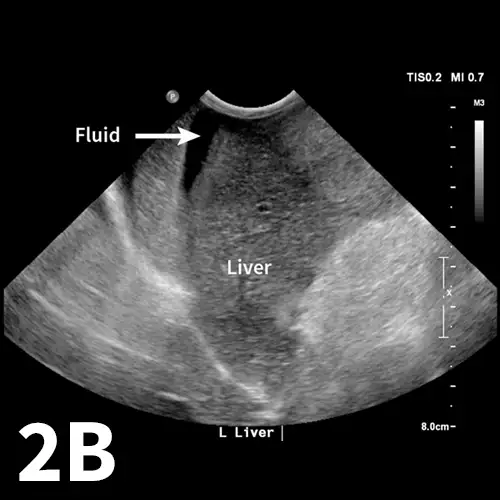

The aFAST examination divides the abdomen into 4 quadrants. A good way to perform the examination is to use a clock-face analogy and begin at the 12-o’clock position (Clock-face). The starting position, designated the diaphragmatic–hepatic (DH) position, is caudal to the xiphoid process; it is useful for finding fluid between liver lobes and the diaphragm. The next quadrant lies at the 3-o’clock position over the left flank and is designated the spleno–renal (SR) position. Both the spleen and left kidney should be visible within this region. At the 6-o’clock position over the caudal abdomen, the urinary bladder and colon can be seen, making this window the cysto–colic (CC) position. The final quadrant within the aFAST examination is over the right flank at the 9-o’clock position, designated the hepato–renal (HR) position. The right kidney and liver should be visible within this region.1,4

Applying the abdominal fluid scoring (AFS) system when evaluating each quadrant of the abdomen during the aFAST examination may be useful. The AFS is a 4-point scale that starts at 0 (negative for peritoneal fluid). One point is assigned for each quadrant in which fluid is identified, up to 4 points total. The amount of fluid in a particular quadrant does not affect the score (ie, any amount of fluid, minimal-to-severe, receives the same point value of 1). It is important to note that AFS scores are only validated in dogs when the examination is performed with the patient in right lateral recumbency. Dogs with AFS scores of 3 and 4 are more likely to require blood transfusions compared with dogs with AFS scores of 0 to 2.4

As with many skills in veterinary medicine, becoming proficient at the aFAST examination and maneuvering the ultrasound probe requires practice. The aFAST examination can be easy to learn and a good way to identify peritoneal fluid in patients with recent motor vehicle trauma. The aFAST examination also has applications in patients that present with an acute abdomen but no known trauma. With gained proficiency, clinicians may be able to diagnose other conditions (eg, splenic mass, gallbladder mucocele) that could require acute intervention.